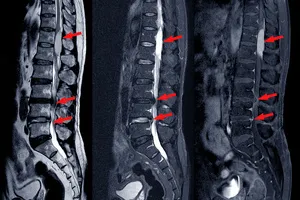

3. 척추 압박 골절

척추 압박 골절은 주로 골다공증 환자에게 발생하며, 척추뼈가 납작하게 찌그러져 심한 허리 통증을 유발하는 질환입니다. 가벼운 충격이나 외상, 스테로이드 약물 복용 등이 원인이 될 수 있습니다. 침상 안정, 약물 치료, 보조기 착용, 물리치료 등의 보존적인 치료와 함께 경피적 척추 성형술이나 척추 고정술과 같은 수술적 치료가 필요할 수 있습니다. 골다공증 예방을 위해 칼슘과 비타민 D 섭취, 규칙적인 운동, 금연 등이 중요합니다.

5. 척추관 협착증

척추관 협착증은 척추관이 좁아져 신경이 눌리면서 발생하는 질환으로, 허리 통증과 함께 다리 저림, 보행 시 통증이 심해지는 것이 특징입니다. 장시간 서 있거나 걸을 때 증상이 악화되는 경우가 많습니다. 척추관 협착증은 노화, 퇴행성 변화 등 다양한 원인에 의해 발생하며, 조기 진단과 치료가 중요합니다.